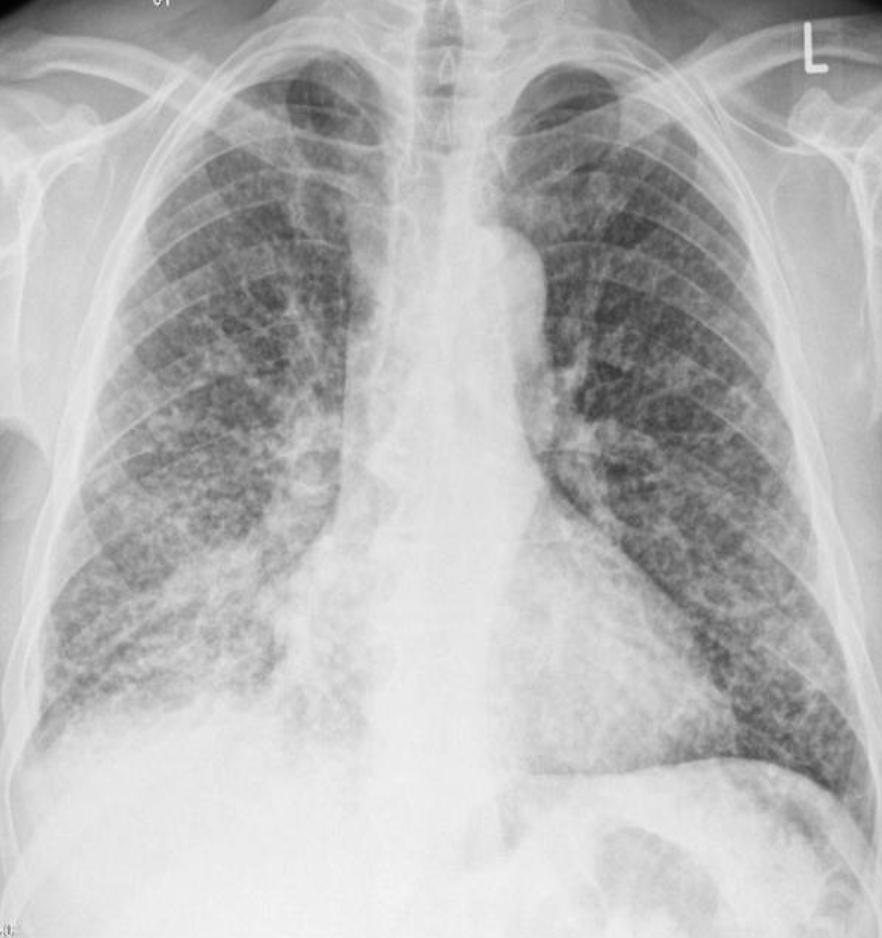

32 year female presented with fever & weight loss

Describe radiological findings

What’s the abnormal here? You should read the whole chest film PA VIEW:

- The trachea looks central.

- Heart looks normal in shape and size.

- What’s abnormal? You have all this reticular shadows and nodules all over the lungs,

Bronchitis does not give a picture like this while miliary TB is a possibility.

differential diagnosis of miliary shadow of the lung?

1- Miliary TB

2- Sarcoid

3- Diffuse metastatic lesions.

4- Lymphomas

5- Silicosis

32 year male presented with fever & weight loss

-

Describe radiological findings?

a. Miliary shadow

b. Bilateral reticular shadow—with sligh tracheal deviation to the right -

List two causes?

a. Miliary TB

b. Fungal infection